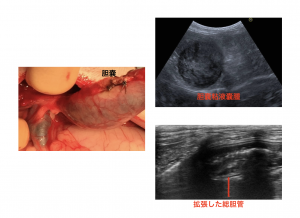

特に今回は胆嚢の病気の中でも比較的多く見られる胆嚢粘液囊腫(たんのうねんえきのうしゅ)についてご紹介します。胆嚢粘液囊腫とは胆汁がドロドロになるため胆汁が流れなくなり総胆管という管がつまる状態で放っておくと死んでしまう怖い病気です(>o<)

胆汁の流れが悪くなっているかどうかは超音波で確認し総胆管の拡張があるかどうかを確認します

胆のう切除後元気になったカゲトラ君です↓↓